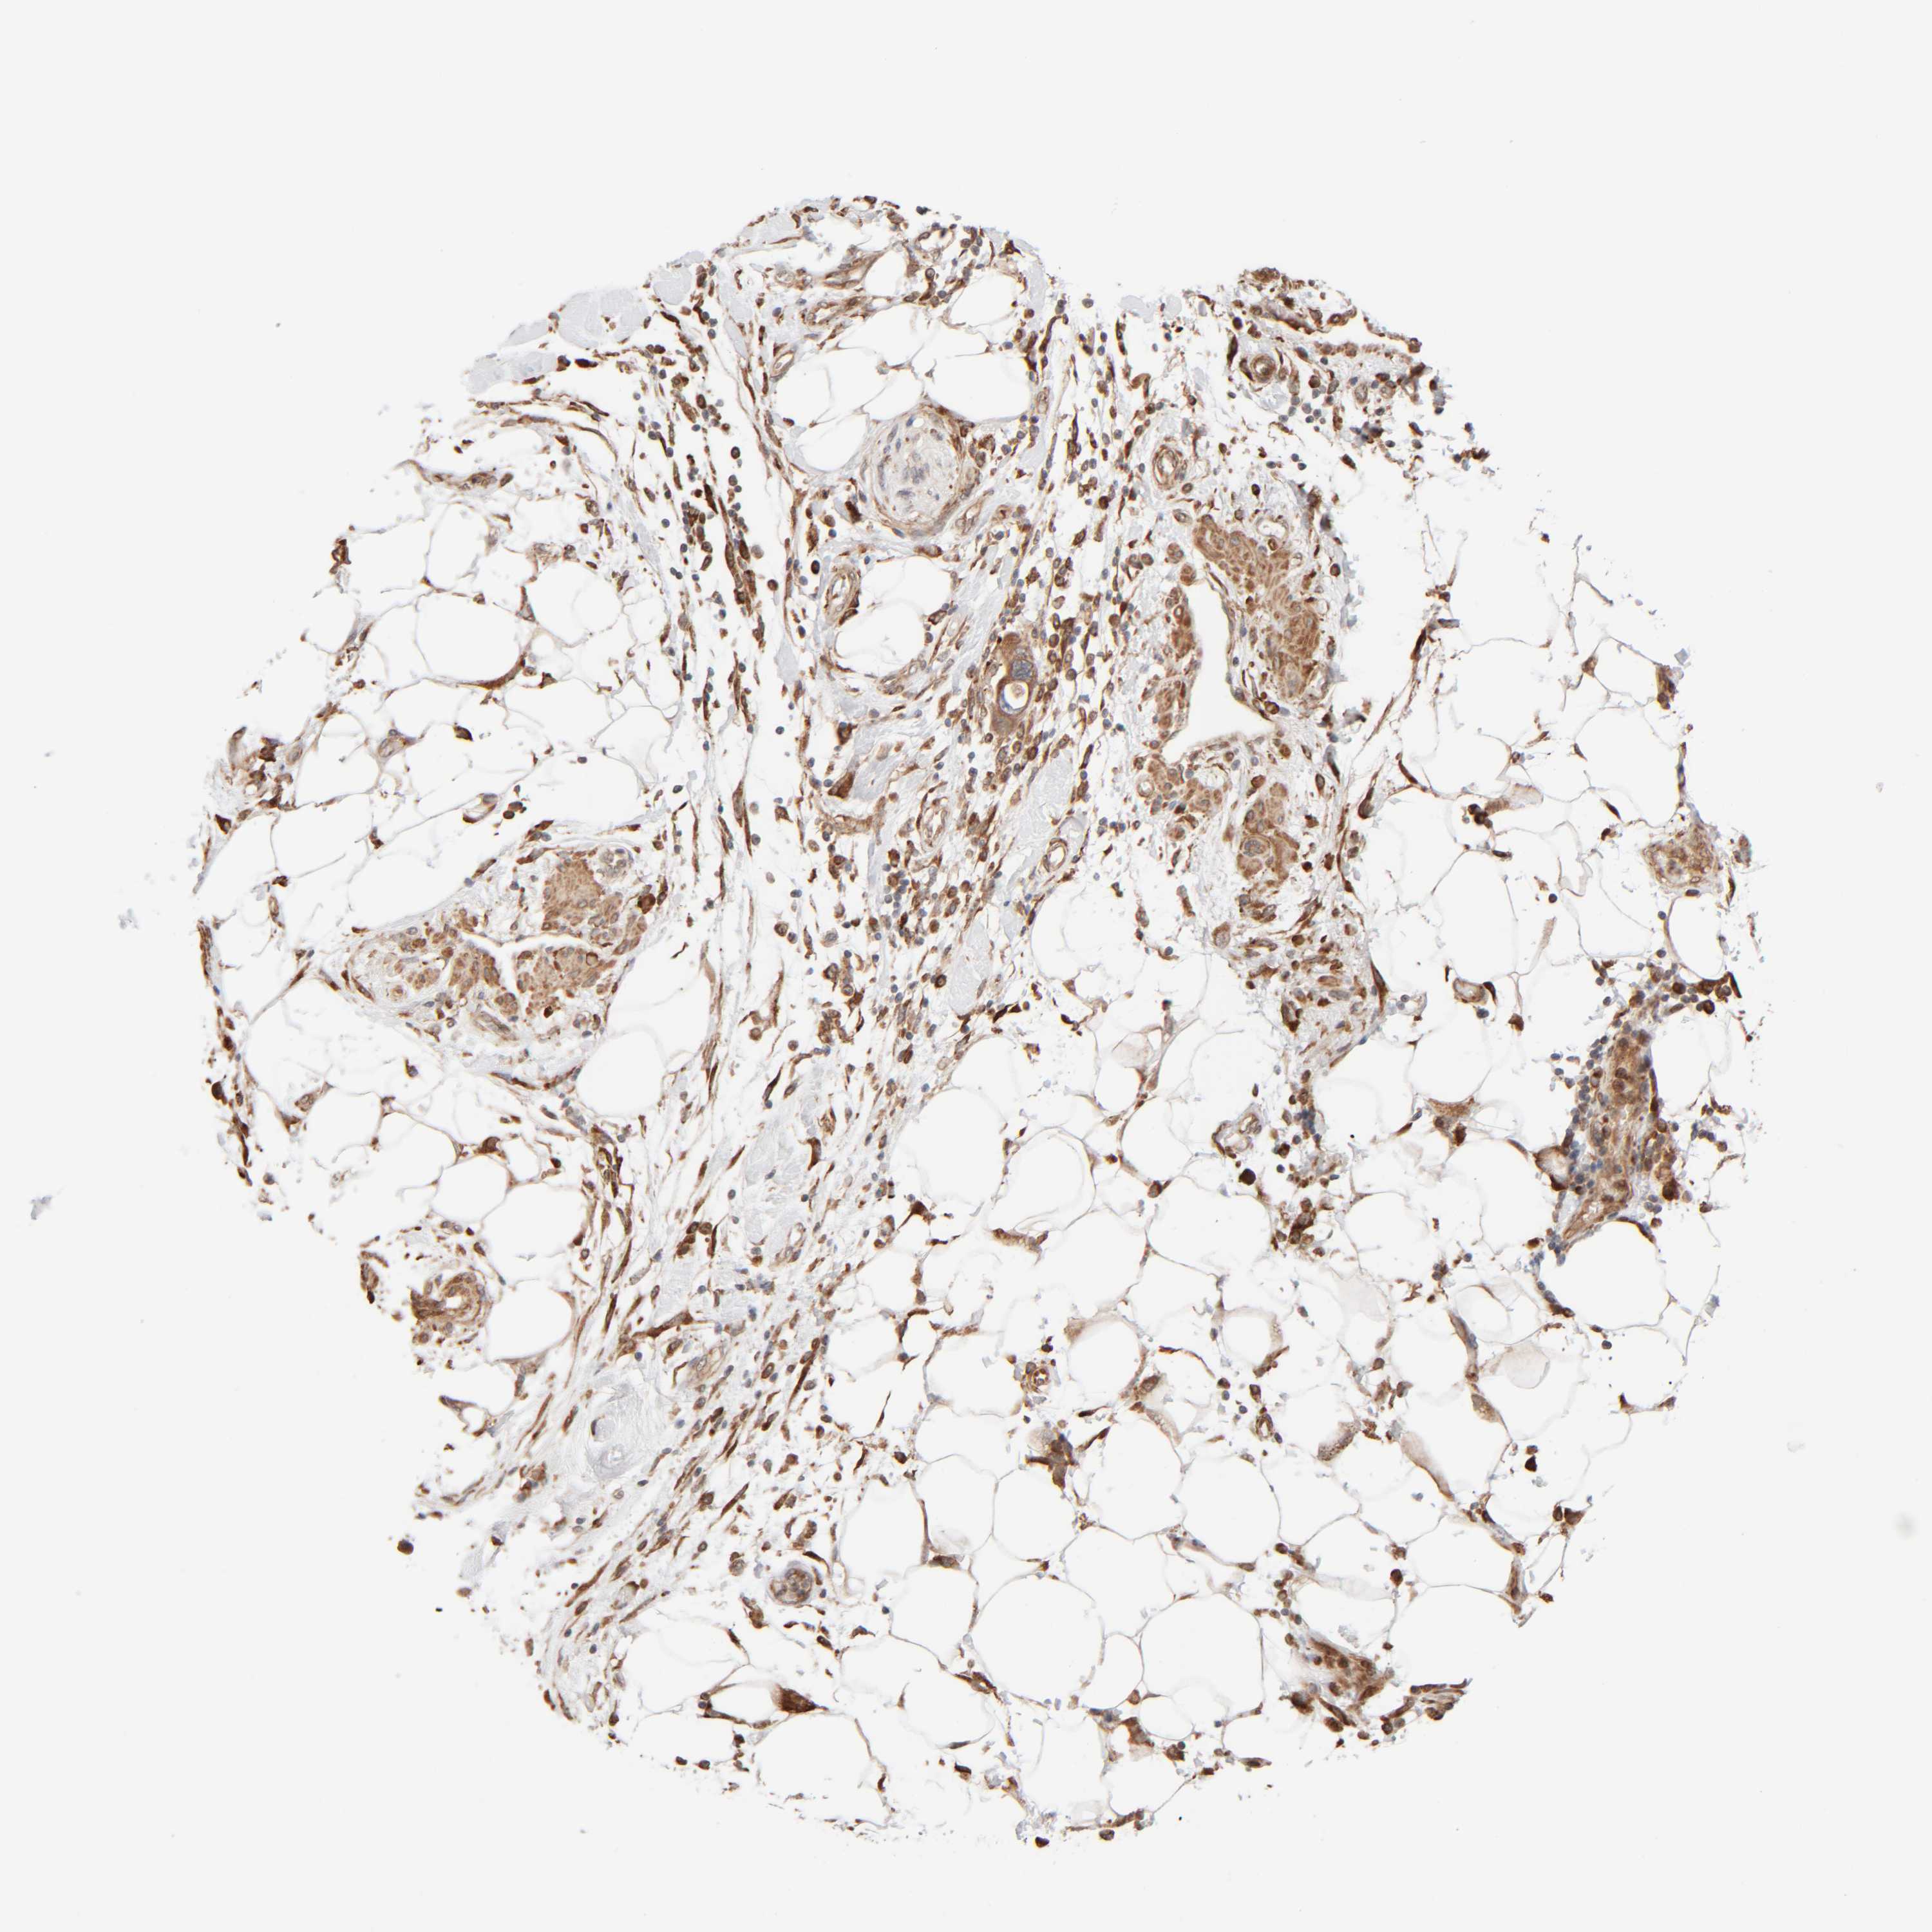

PANCREATIC CANCER - Protein expressioni

A mouse-over function shows sample information and annotation data. Click on an image to view it in a full screen mode. Samples can be filtered based on level of antibody staining by selecting one or several of the following categories: high, medium, low and not detected. The assay and annotation is described here.

Note that samples used for immunohistochemistry by the Human Protein Atlas do not correspond to samples in the TCGA dataset.

Antibody stainingi

Antibody staining in the annotated cell types in the current human tissue is reported as not detected, low, medium, or high, based on conventional immunohistochemistry profiling in selected tissues. This score is based on the combination of the staining intensity and fraction of stained cells.

Each image is clickable and will lead to virtual microscopy that enables deeper exploration of all samples and also displays staining intensity scores, fraction scores and subcellular localization as well as patient and tissue information for each sample.

Antibody HPA021658

Staining

High

Medium

Low

Not detected

Intensity

Strong

Moderate

Weak

Negative

Quantity

>75%

75%-25%

<25%

None

Location

Nuclear

Cytoplasmic/membranous

Cytoplasmic/membranous,nuclear

Adenocarcinoma, NOS